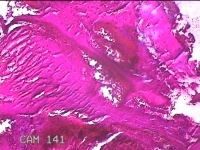

宫颈管内膜组织

性别

女

年龄

39岁

临床诊断

子宫异常出血 子宫内膜不典型增生?子宫内膜占位性病变待查 慢性宫颈炎

一般病史

阴道流血3天,增多1小时。

标本名称

大体所见

灰白暗红色不规则碎组织1.8x1.3x0.3cm一堆。

子宫颈管内膜和子宫内膜组织,没有什么大问题。